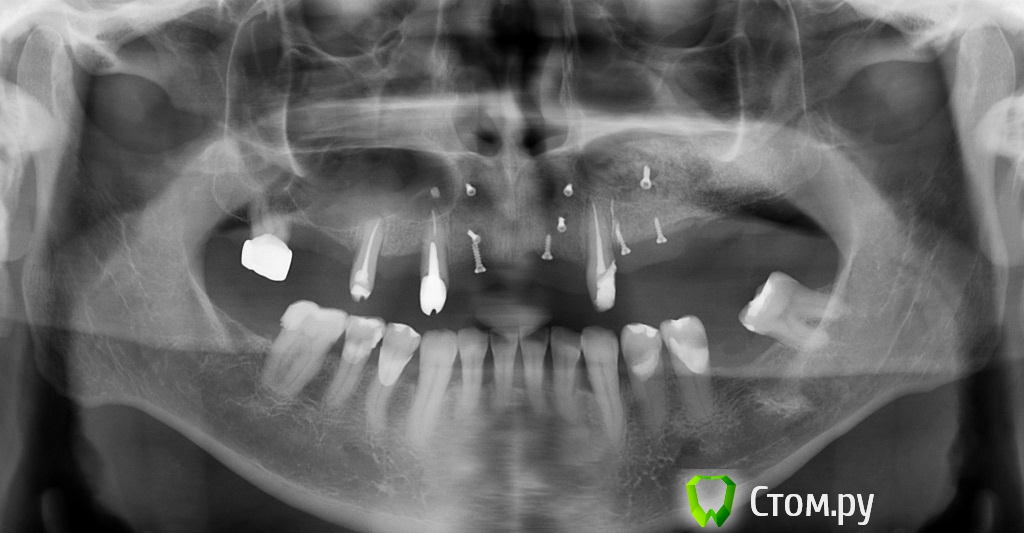

zzkz Опубликовано 2 сентября, 2014 Поделиться Опубликовано 2 сентября, 2014 (изменено) Запланировал сделать все сразу-фронт, слева и справа.На правую сторону не пошел, кончились стерильные винты 1. Синус от 2.4 до 2.7, НКР в области 242. НКР от 1.2 до 2.2 В пазуху ушло 2 мп3, 2 биоса При установке ламины винт прорезался, заштопал Еще раз прорезался винт и еще раз.. Помоему в пазуху переборщил с материалом? Фото кровавые, корявые, не знаю как вы делаете все чистенько. Спасибо болшое, что на форум выкладываете как можно бороться с непредвиденными ситуациями, в частности заплатка на ламину. Что бы делал если не показывали Жду критики.Как бы вы поступили при схожем случае? Изменено 2 сентября, 2014 пользователем zzkz 8 Ссылка на комментарий